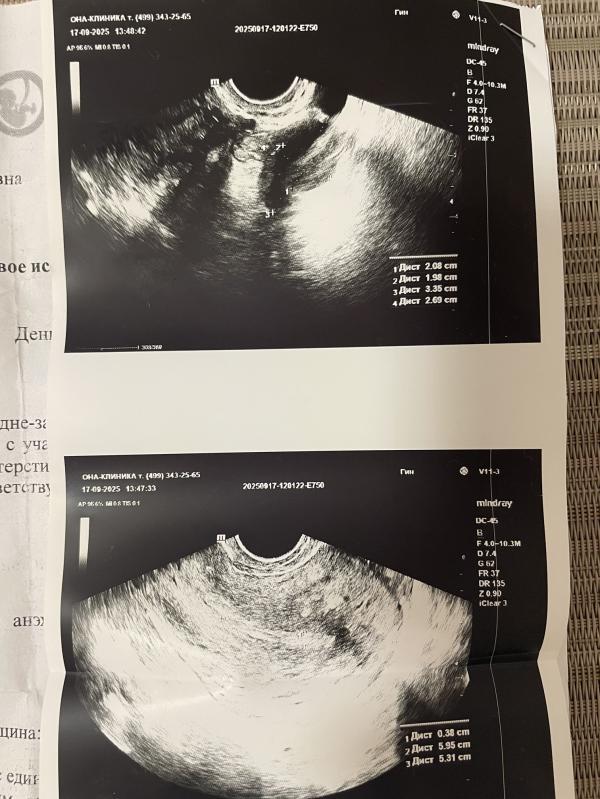

Кто разбирается? Нормально для 4 дц? Врач предположил бхб, всё вышло ( Что там с яичниками? Сказал должны эти кисты пройти к следующему циклу.

Не считая кист , миомы и аденомиоза - всё нормально. Полипов нет, гиперплазии нет.